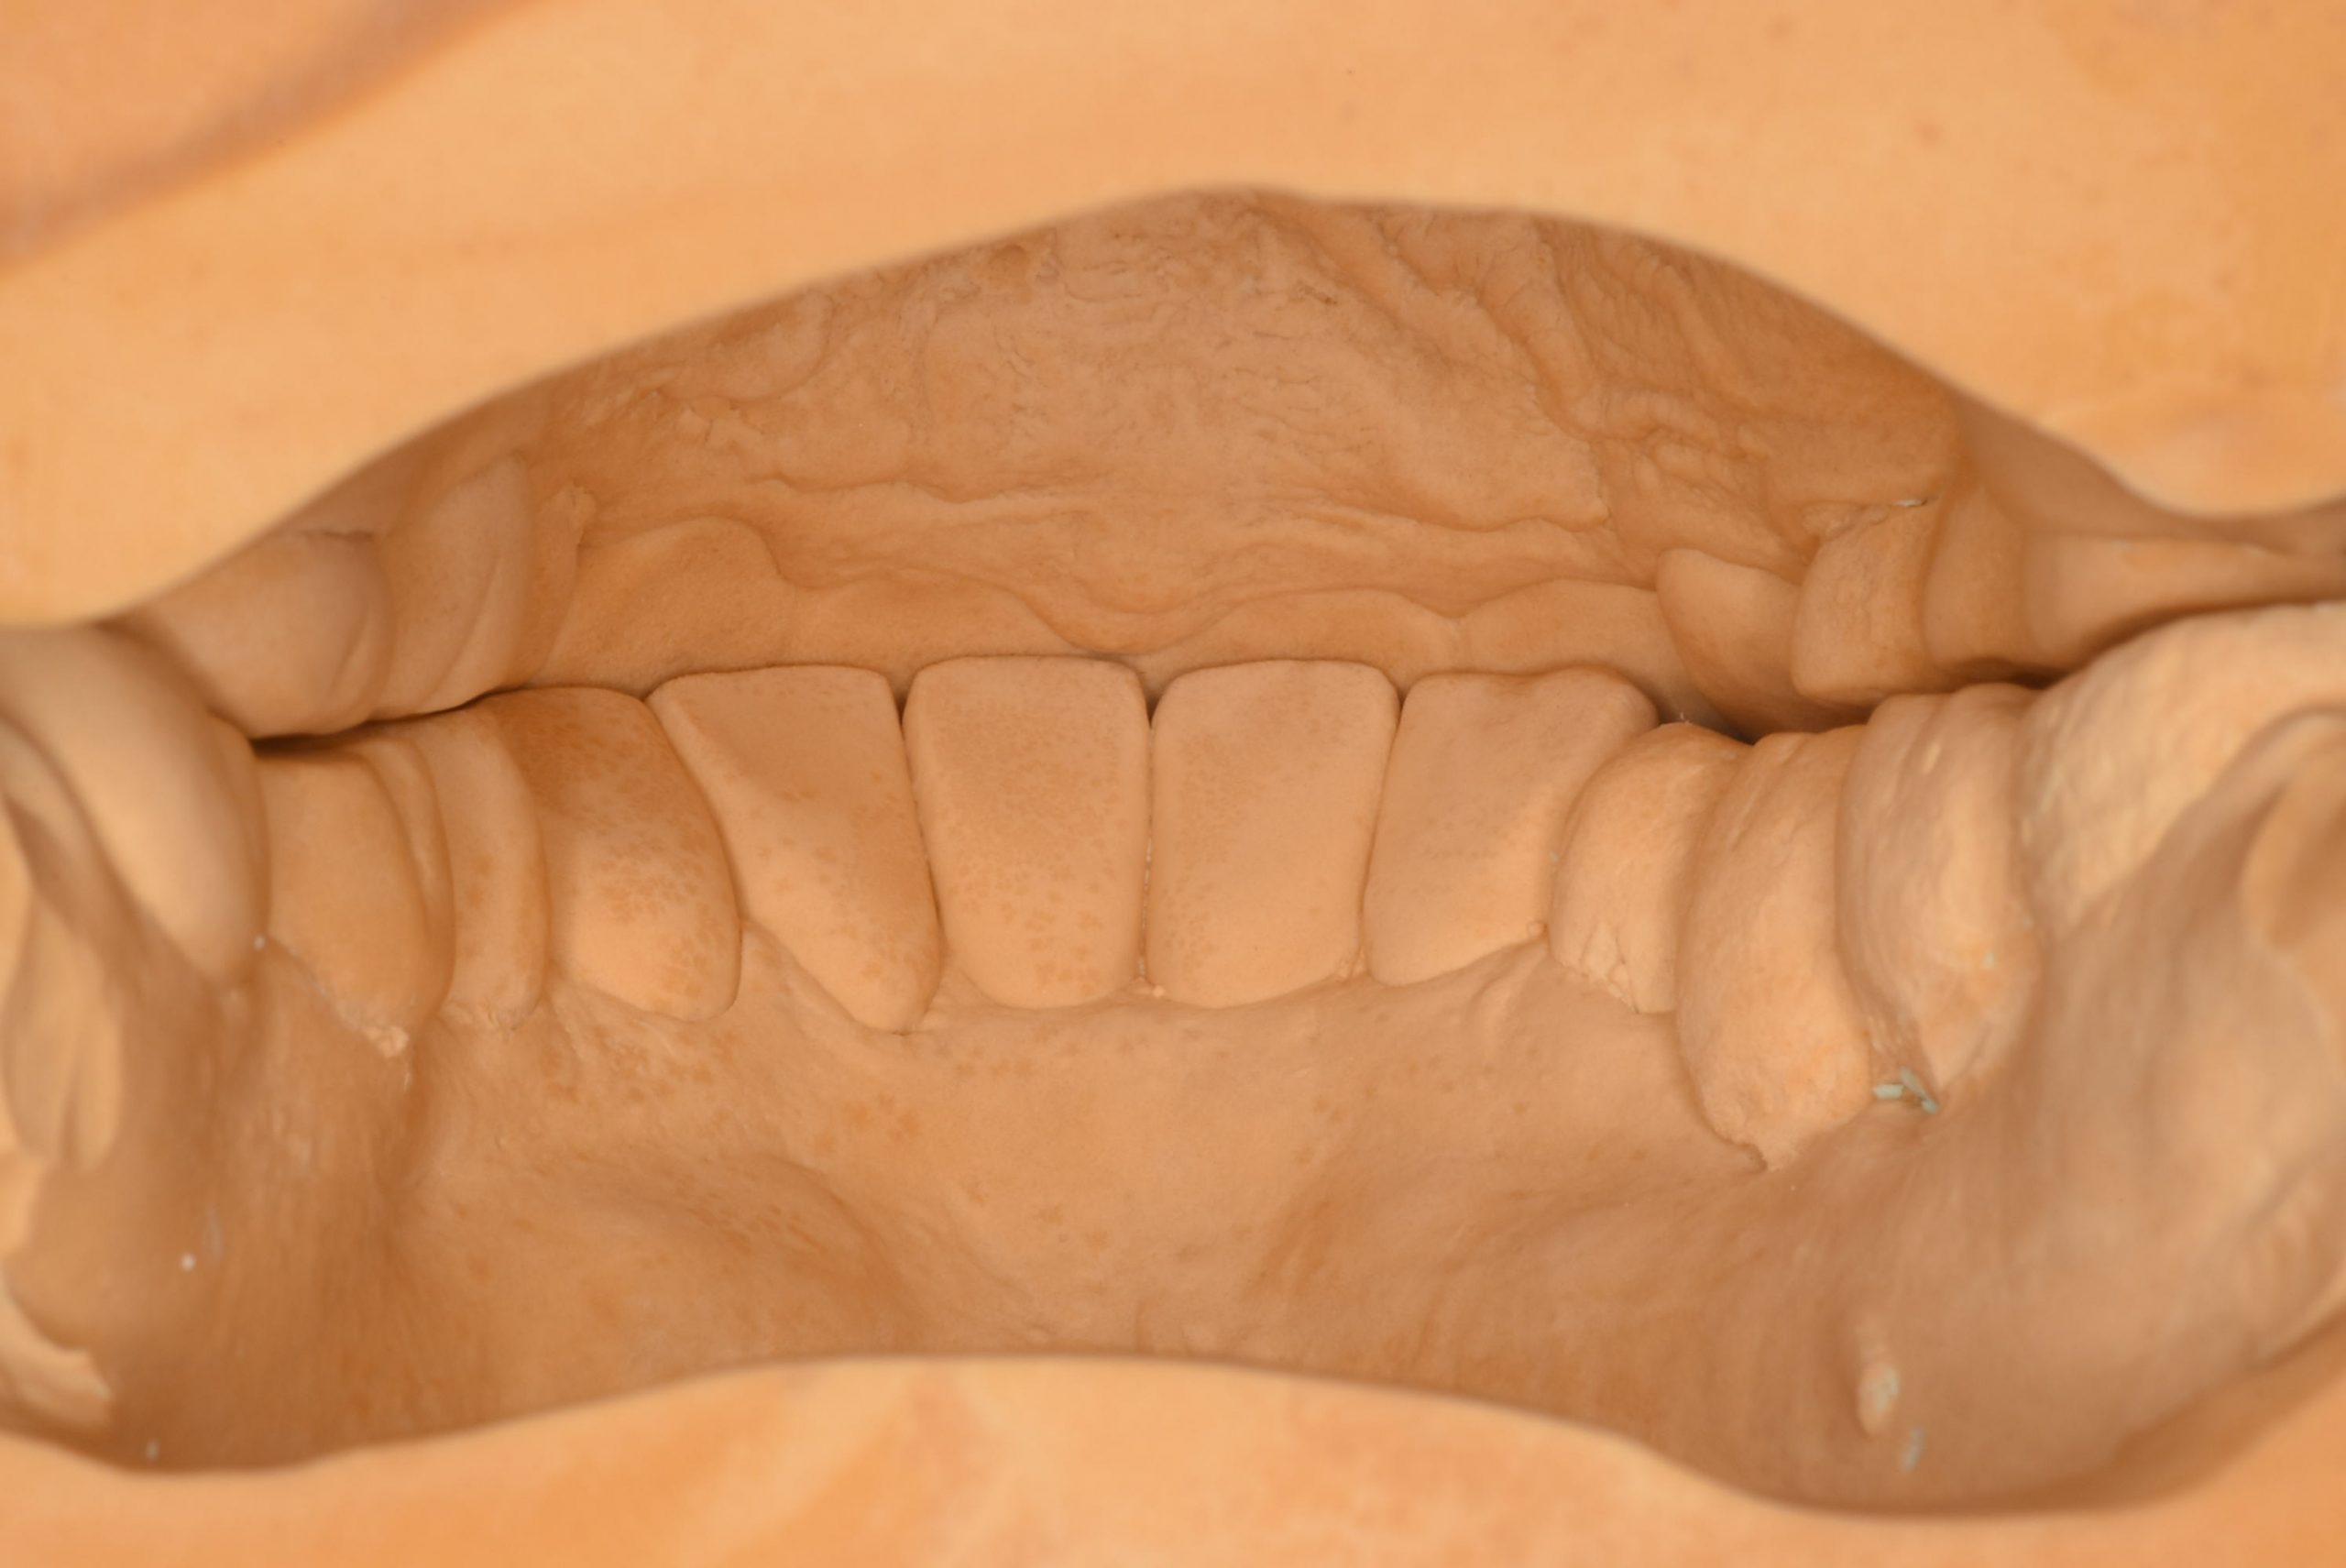

そこで、重要なのが、模型です。

お口の中では、後ろから見ることはできませんが、模型にすると、噛み合わせを後ろから確認できます。

この模型を参考にして、お口の中に入れた時に噛み合わせが合った被せ物を作ります。

これが、そのワックスアップ(歯を作る前の工程)です。